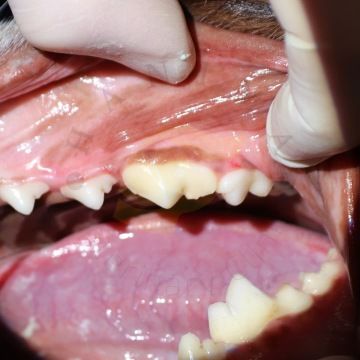

akutní fraktura zubu s expozicí dřeně - komplikovaná fraktura korunky

Trauma zubů je u společenských zvířat bohužel běžná a je často důsledkem nevhodných žvýkacích hraček nebo agresivního chování při žvýkání a hraní. V mnoha případech má zlomený zub obnaženou dřeň. Pokud je trauma čerstvé (trvá méně než 48 hodin), lze zvolit terapii vitální amputace pulpy, aby zub zůstal živý. To je zvláště důležité u mladých zvířat, která mohou mít zuby s nedokončeným vývojem kořene (hrot kořene ještě není uzavřen). V případě téměř expozice dřeň není aktivně vystavena vnějšímu prostředí. Na dřeni je sice stále velmi tenká vrstva dentinu, ale zde existuje vysoké riziko nevratné pulpitidy (pro zvíře bolestivý stav). Třetí možností využití terapie vitální amputace pulpy je v případech liguovezních mandibulárních špičáku (spodné špičáky jsou vyhnuté směrem dovnitř k jazyku) jako ortodontická procedura. Takhle rotované spodní špičáky následně zraňují tvrdé patro zvířete a můžou následně způsobit oronazální píštěl. Oronazální píštěl je abnormální komunikace mezi dutinou ústní a nosní, která vede k chronickým infekcím horních cest dýchacích. Provedením redukce korunky a terapie vitální amputace pulpy na dolních špičácích je dosaženo bezbolestné okluze bez ztráty těchto funkčně důležitých zubů.